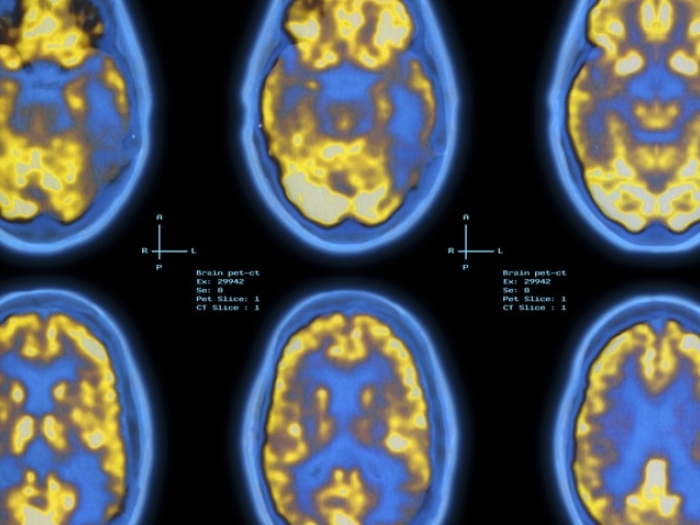

‘Game-Changing’ Alzheimer’s Drug Just a First Step

Despite Lack of Evidence, 10 States Allow Medical Marijuana for Alzheimer’s

Illusions, Hallucinations and Delusions: How to Spot Dementia Symptoms

Alzheimer’s: Not Just a Disease for Older Adults